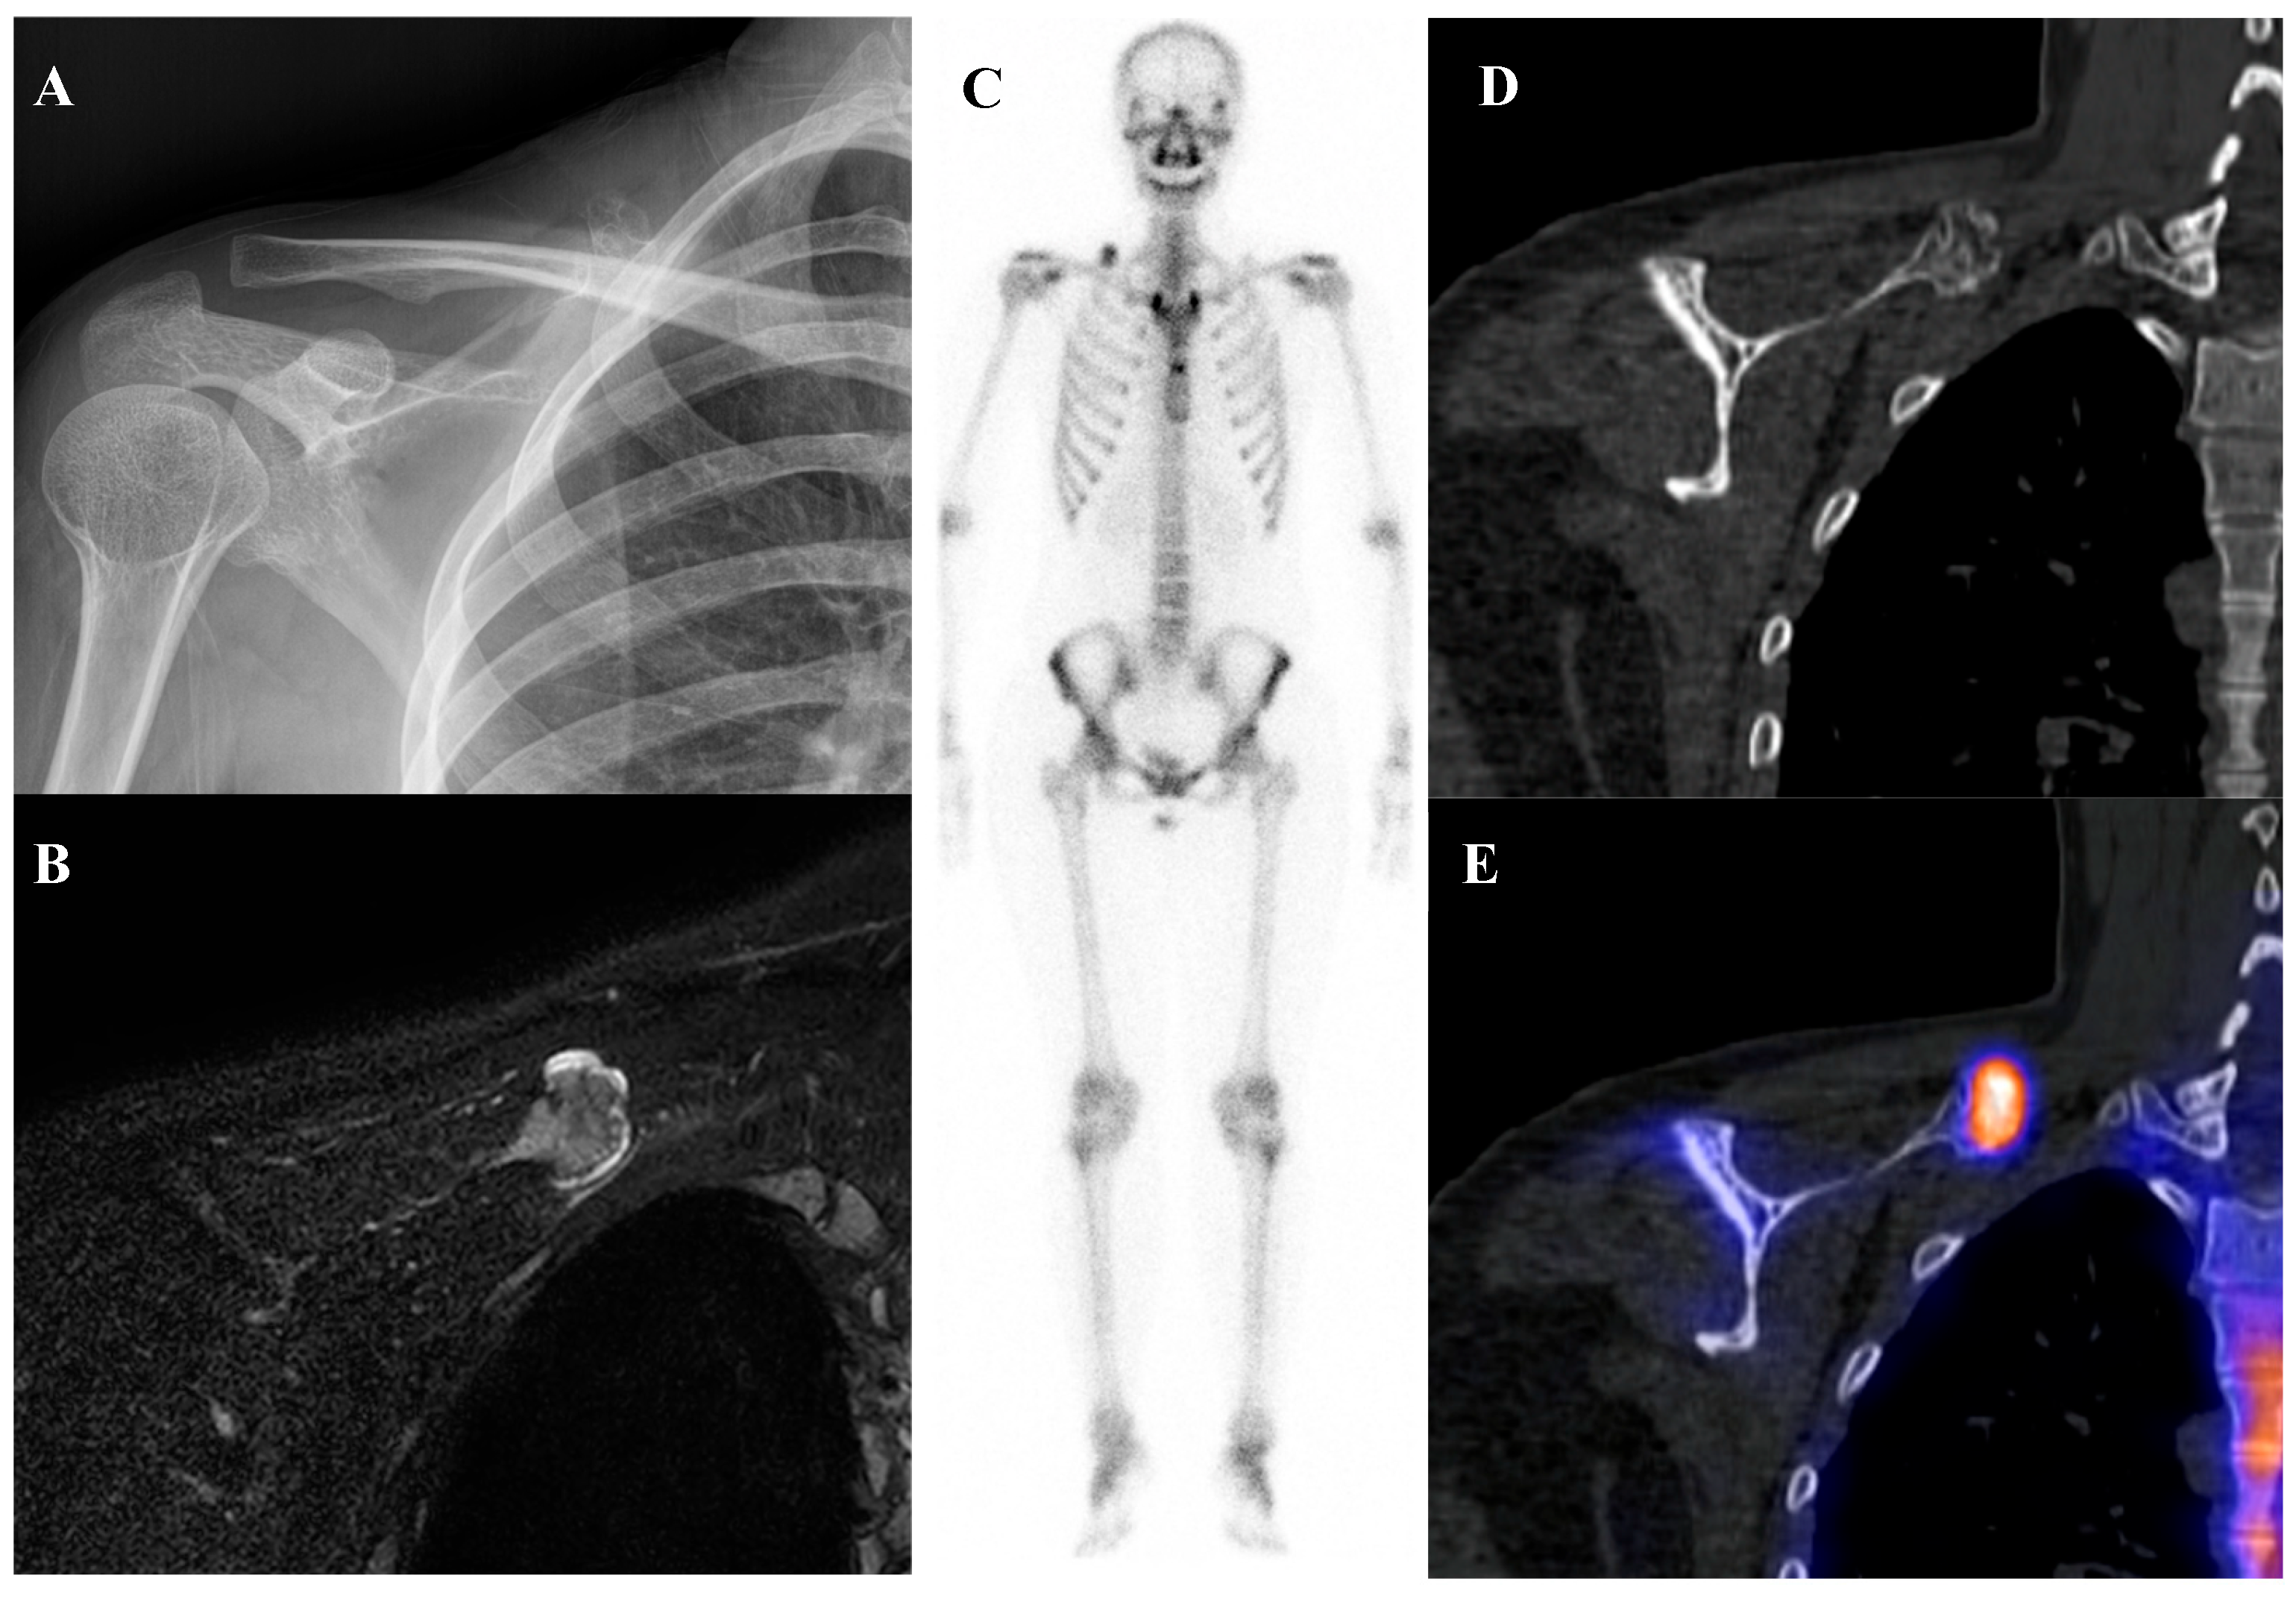

Perhaps the most critical role for [18F]FDG PET/CT in osteosarcoma management is in the evaluation of response to neoadjuvant chemotherapy. The standard of care for high-grade osteosarcoma involves preoperative chemotherapy followed by surgical resection. The degree of tumor necrosis in the resected specimen is one of the most powerful prognostic factors. A “good response,” defined as ≥90% tumor necrosis, is associated with a much better prognosis than a “poor response” (<90% necrosis). [18F]FDG PET/CT perfor-med before and after neoadjuvant chemotherapy can non-invasively predict this histologic response. A significant reduction in the tumor’s SUVmax following chemotherapy is a robust indicator of a good pathologic response [15,37,38,39,40,41,42,43]. This information can help predict prognosis and guide critical therapeutic decisions. Figure 1 demonstrates a representative case in which marked reduction of [18F]FDG uptake after chemotherapy corresponded to predominantly necrotic tissue in the resected specimen, resulting in long-term disease-free survival. This information can help predict prognosis and guide critical therapeutic decisions.

Figure 1.

A 16-year-old male with osteosarcoma of the right distal femur. (A) Pretreatment bone scintigraphy shows intense uptake in the distal femoral metaphysis. (B,C) Pretreatment [18F]FDG positron emission tomography/computed tomography demonstrates a heterogeneous, [18F]FDG-avid mass with cortical breakthrough and soft-tissue extension (SUVmax 12.6). (D,E) After neoadjuvant chemotherapy, [18F]FDG uptake markedly decreased (SUVmax 2.3) with reduction in tumor extent. (F) Wide excision specimen (×40) revealed predominantly necrotic tissue, confirming a marked response to chemotherapy, in contrast to (G) the pretreatment biopsy specimen (×100) with viable malignant cells. He has remained disease-free for 8 years.